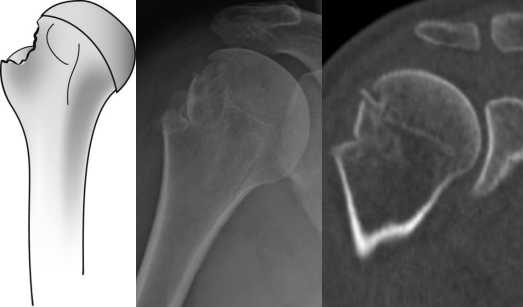

影像学诊断

单纯大结节骨折移位较大甚至突入肱骨头及肩峰之间。